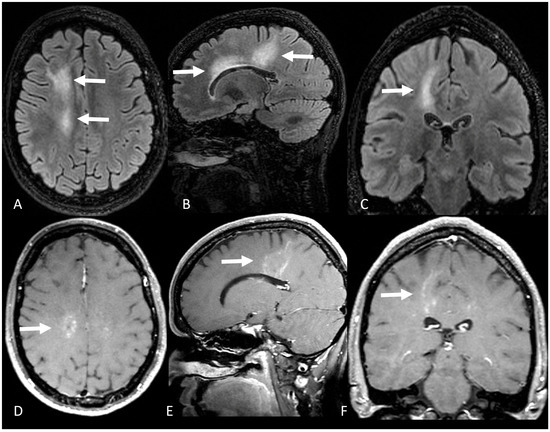

| Location | N/A 1 | Bilateral PVWM lesions, including the amygdala and hippocampus | Right occipital lobe, right precentral gyrus, and multiple small lesions in PVWM | Subcortical and PVWM lesions in the right frontoparietal and insular lobes | Right parieto-occipital subcortical and PVWM, extending to the splenium |